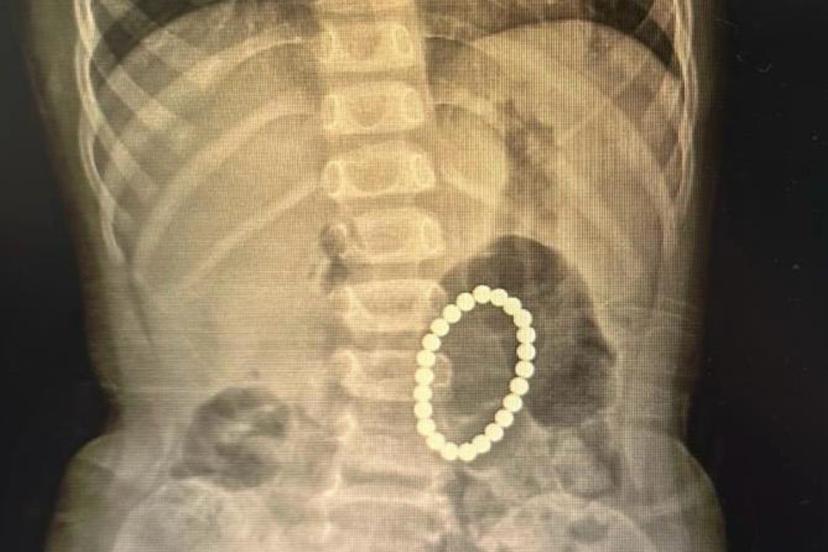

Çocuklarda sık karşılaşılan risklere değinen Özkaya "Günlük hayatta çocuklarda sık karşılaşılan yabancı cisim yutulması, kimyasal madde içilmesi ve solunum yollarına yabancı cisim kaçması önemli sağlık sorunları arasında yer almaktadır. Özellikle ilk üç yaşındaki çocuklar, yerde buldukları nesneleri ağızlarına götürme eğilimindedir. Madeni paralar, disk piller, iğneler ve küçük oyuncak parçaları çocuklar tarafından yutulabilmekte; bu maddeler yemek borusuna ya da solunum yollarına kaçabilmektedir. Bu tür durumlarda ailelerin olaya şahit olmaları hâlinde çocuğun ağzını kontrol etmeleri, yutma şüphesi varsa vakit kaybetmeden en yakın sağlık kuruluşuna başvurmaları gerekmektedir." dedi.

Solunum yollarına yabancı cisim kaçmasının da önemli bir risk olduğuna dikkat çeken Özkaya "Solunum yollarına yabancı cisim kaçması da günlük hayatta sık karşılaşılan ve hayati tehlike oluşturabilen durumlardan biridir. Özellikle üç yaşına kadar olan çocuklara çerez, fındık, fıstık, çekirdek gibi sert gıdaların verilmemesi gerekmektedir. Bu gıdalar solunum yollarına kaçarak ciddi nefes darlığına neden olabilmektedir. Böyle bir durumla karşılaşıldığında, mümkünse Heimlich manevrası uygulanmalı ve 112 Acil Servis eşliğinde en yakın sağlık kuruluşuna başvurulmalıdır. Bu tür vakaların operasyon gerektirebileceğine dikkat çekilerek, özellikle yemek borusunda kalan disk pillerin son derece tehlikeli olduğu vurgulanmaktadır. Disk piller, çocukta belirgin bir şikâyet olmasa bile kısa sürede yemek borusunda yanıklara ve delinmelere yol açabilmekte, hayati risk oluşturabilmektedir. Bu nedenle acil olarak ameliyathane ortamında çıkarılmaları gerekmektedir." şeklinde konuştu.